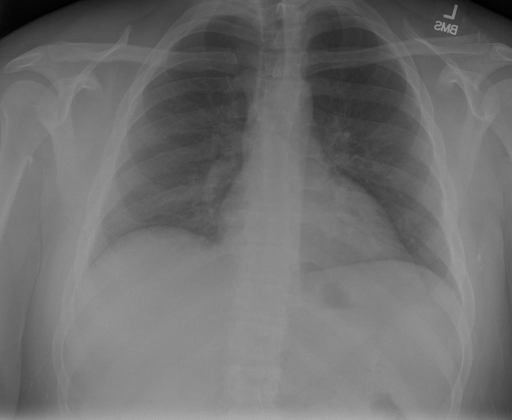

# 本文贡献  - 借助ChatGPT以及公开的数据集,我们构造了一个`X光影像-诊断报告`对的医学多模态数据集; # 数据集 - [MIMIC-CXR](https://physionet.org/content/mimic-cxr-jpg/2.0.0/)是一个公开可用的胸部X光片数据集,包括377,110张图像和227,827个相关报告。 - [OpenI](https://openi.nlm.nih.gov/faq#collection)是一个来自印第安纳大学医院的胸部X光片数据集,包括6,459张图像和3,955个报告。 在上述工作中,报告信息都为非结构化的,不利于科学研究。为了生成合理的医学报告,我们对两个数据集进行了预处理,并最终得到了可以用于训练的**英文报告**。除此之外,为了更好的支持中文社区发展,借助ChatGPT的能力,我们将英文报告进行了中文翻译,并最终形成了可用于训练的数据集。 |数据集|数量|下载链接| |:-|:-|:-| |MIMIC-CXR-zh|-|-| |OpenI-zh|6,423|[诊疗报告](./data/Xray/openi-zh.json) 、[X光影像](https://pan.baidu.com/s/13GBsDMKf6xBZBSHpoWH_EA?pwd=k9sh)| # 快速上手 1. 安装环境 ```bash # 安装依赖 pip install -r requirements.txt # 国内换源安装依赖 pip install -i https://mirrors.aliyun.com/pypi/simple/ -r requirements.txt ``` 此时默认会安装`deepspeed`库(支持`sat`库训练),此库对于模型推理并非必要,同时部分`Windows`环境安装此库时会遇到问题。 如果想绕过`deepspeed`安装,我们可以将命令改为: ```bash # 安装依赖 pip install -i https://mirrors.aliyun.com/pypi/simple/ -r requirements_wo_ds.txt # 安装SwissArmyTransformer pip install -i https://mirrors.aliyun.com/pypi/simple/ --no-deps "SwissArmyTransformer>=0.3.6" ``` 2. 模型推理 CLI推理: ```python python cli_demo.py --from_pretrained checkpoints/finetune-XrayGLM-05-25-01-04 --prompt_zh '详细描述这张胸部X光片的诊断结果' ``` 更多[参数](https://github.com/WangRongsheng/XrayGLM/blob/main/cli_demo.py#L16) # 效果展示 |X光影像|诊疗报告(医生)|XrayGLM| |:-|:-|:-| ||根据X射线图像,心脏大小正常,肺部看起来很清晰。已经排除了肺炎、积液、水肿、气胸、腺病、结节或肿块的存在。该发现表明一切正常。换句话说,总体印象是胸部正常。|X光片显示,心脏大小正常。肺部没有气胸或胸腔积液的证据。骨骼结构看起来没有任何异常。总的来说,X光片表明没有发现急性心肺疾病的迹象。| ||X光图片显示没有扭曲的区域、可疑的骨质不透明度或胸腺积液。心脏大小轻微增大,但非常稳定。此外,没有气胸的证据,肺野也正常。总体来说,X光片显示没有急性心脏异常,但要注意轻微的心脏扩大。|X光片显示,心脏大小正常。肺部和纵隔轮廓清晰,没有气胸或胸腔积液的证据。骨骼结构完整,没有任何急性异常。| ||心影形态在正常范围内。没有急性骨质异常。有可能出现没有明显的吸水或肺实质状况的线索。没有大面积积液或气胸。有可能怀疑其有误吸或肺实质问题。为了确诊和治疗,可能需要进行适当的影像学随访。|心脏大小正常,肺部和纵隔轮廓清晰。没有急性异常或活动受限的证据。没有任何明显的气胸、胸腔积液或肺不张的迹象。此外,也没有发现任何局灶性骨质异常或其他急性疾病。| # 项目致谢 1. [VisualGLM-6B](https://github.com/THUDM/VisualGLM-6B)为我们提供了基础的代码参考和实现; 2. [MiniGPT-4](https://github.com/Vision-CAIR/MiniGPT-4)为我们这个项目提供了研发思路; 3. ChatGPT生成了高质量的中文版X光检查报告以支持XrayGLM训练; 4. [gpt_academic](https://github.com/binary-husky/gpt_academic)为文档翻译提供了多线程加速; 5. [MedCLIP](https://github.com/RyanWangZf/MedCLIP) 、[BLIP2](https://huggingface.co/docs/transformers/main/model_doc/blip-2) 、[XrayGPT](https://github.com/mbzuai-oryx/XrayGPT) 等工作也有重大的参考意义;  这项工作由[澳门理工大学应用科学学院](https://www.mpu.edu.mo/esca/zh/index.php)硕士生[王荣胜](https://github.com/WangRongsheng) 、[段耀菲](https://github.com/IsBaSO4) 、[李俊蓉](https://github.com/lijunrong0815)完成,同时这项工作受到[檀韬](https://scholar.google.com/citations?hl=zh-CN&user=lLg3WRkAAAAJ)副教授、[彭祥佑](http://www.patrickpang.net/)老师的帮助支持。 *特别鸣谢:[USTC-PhD Yongle Luo](https://github.com/kaixindelele) 提供了有3000美金的OpenAI账号,帮助我们完成大量的X光报告翻译工作 # 免责声明 本项目相关资源仅供学术研究之用,严禁用于商业用途。使用涉及第三方代码的部分时,请严格遵循相应的开源协议。模型生成的内容受模型计算、随机性和量化精度损失等因素影响,本项目无法对其准确性作出保证。即使本项目模型输出符合医学事实,也不能被用作实际医学诊断的依据。对于模型输出的任何内容,本项目不承担任何法律责任,亦不对因使用相关资源和输出结果而可能产生的任何损失承担责任。 # 项目引用 如果你使用了本项目的模型,数据或者代码,请声明引用: ```bash @misc{wang2023XrayGLM, title={XrayGLM: The first Chinese Medical Multimodal Model that Chest Radiographs Summarization}, author={Rongsheng Wang, Yaofei Duan, Junrong Li, Patrick Pang and Tao Tan}, year={2023}, publisher = {GitHub}, journal = {GitHub repository}, howpublished = {\url{https://github.com/WangRongsheng/XrayGLM}}, } ``` # 使用许可 此存储库遵循[CC BY-NC-SA](https://creativecommons.org/licenses/by-nc-sa/4.0/) ,请参阅许可条款。